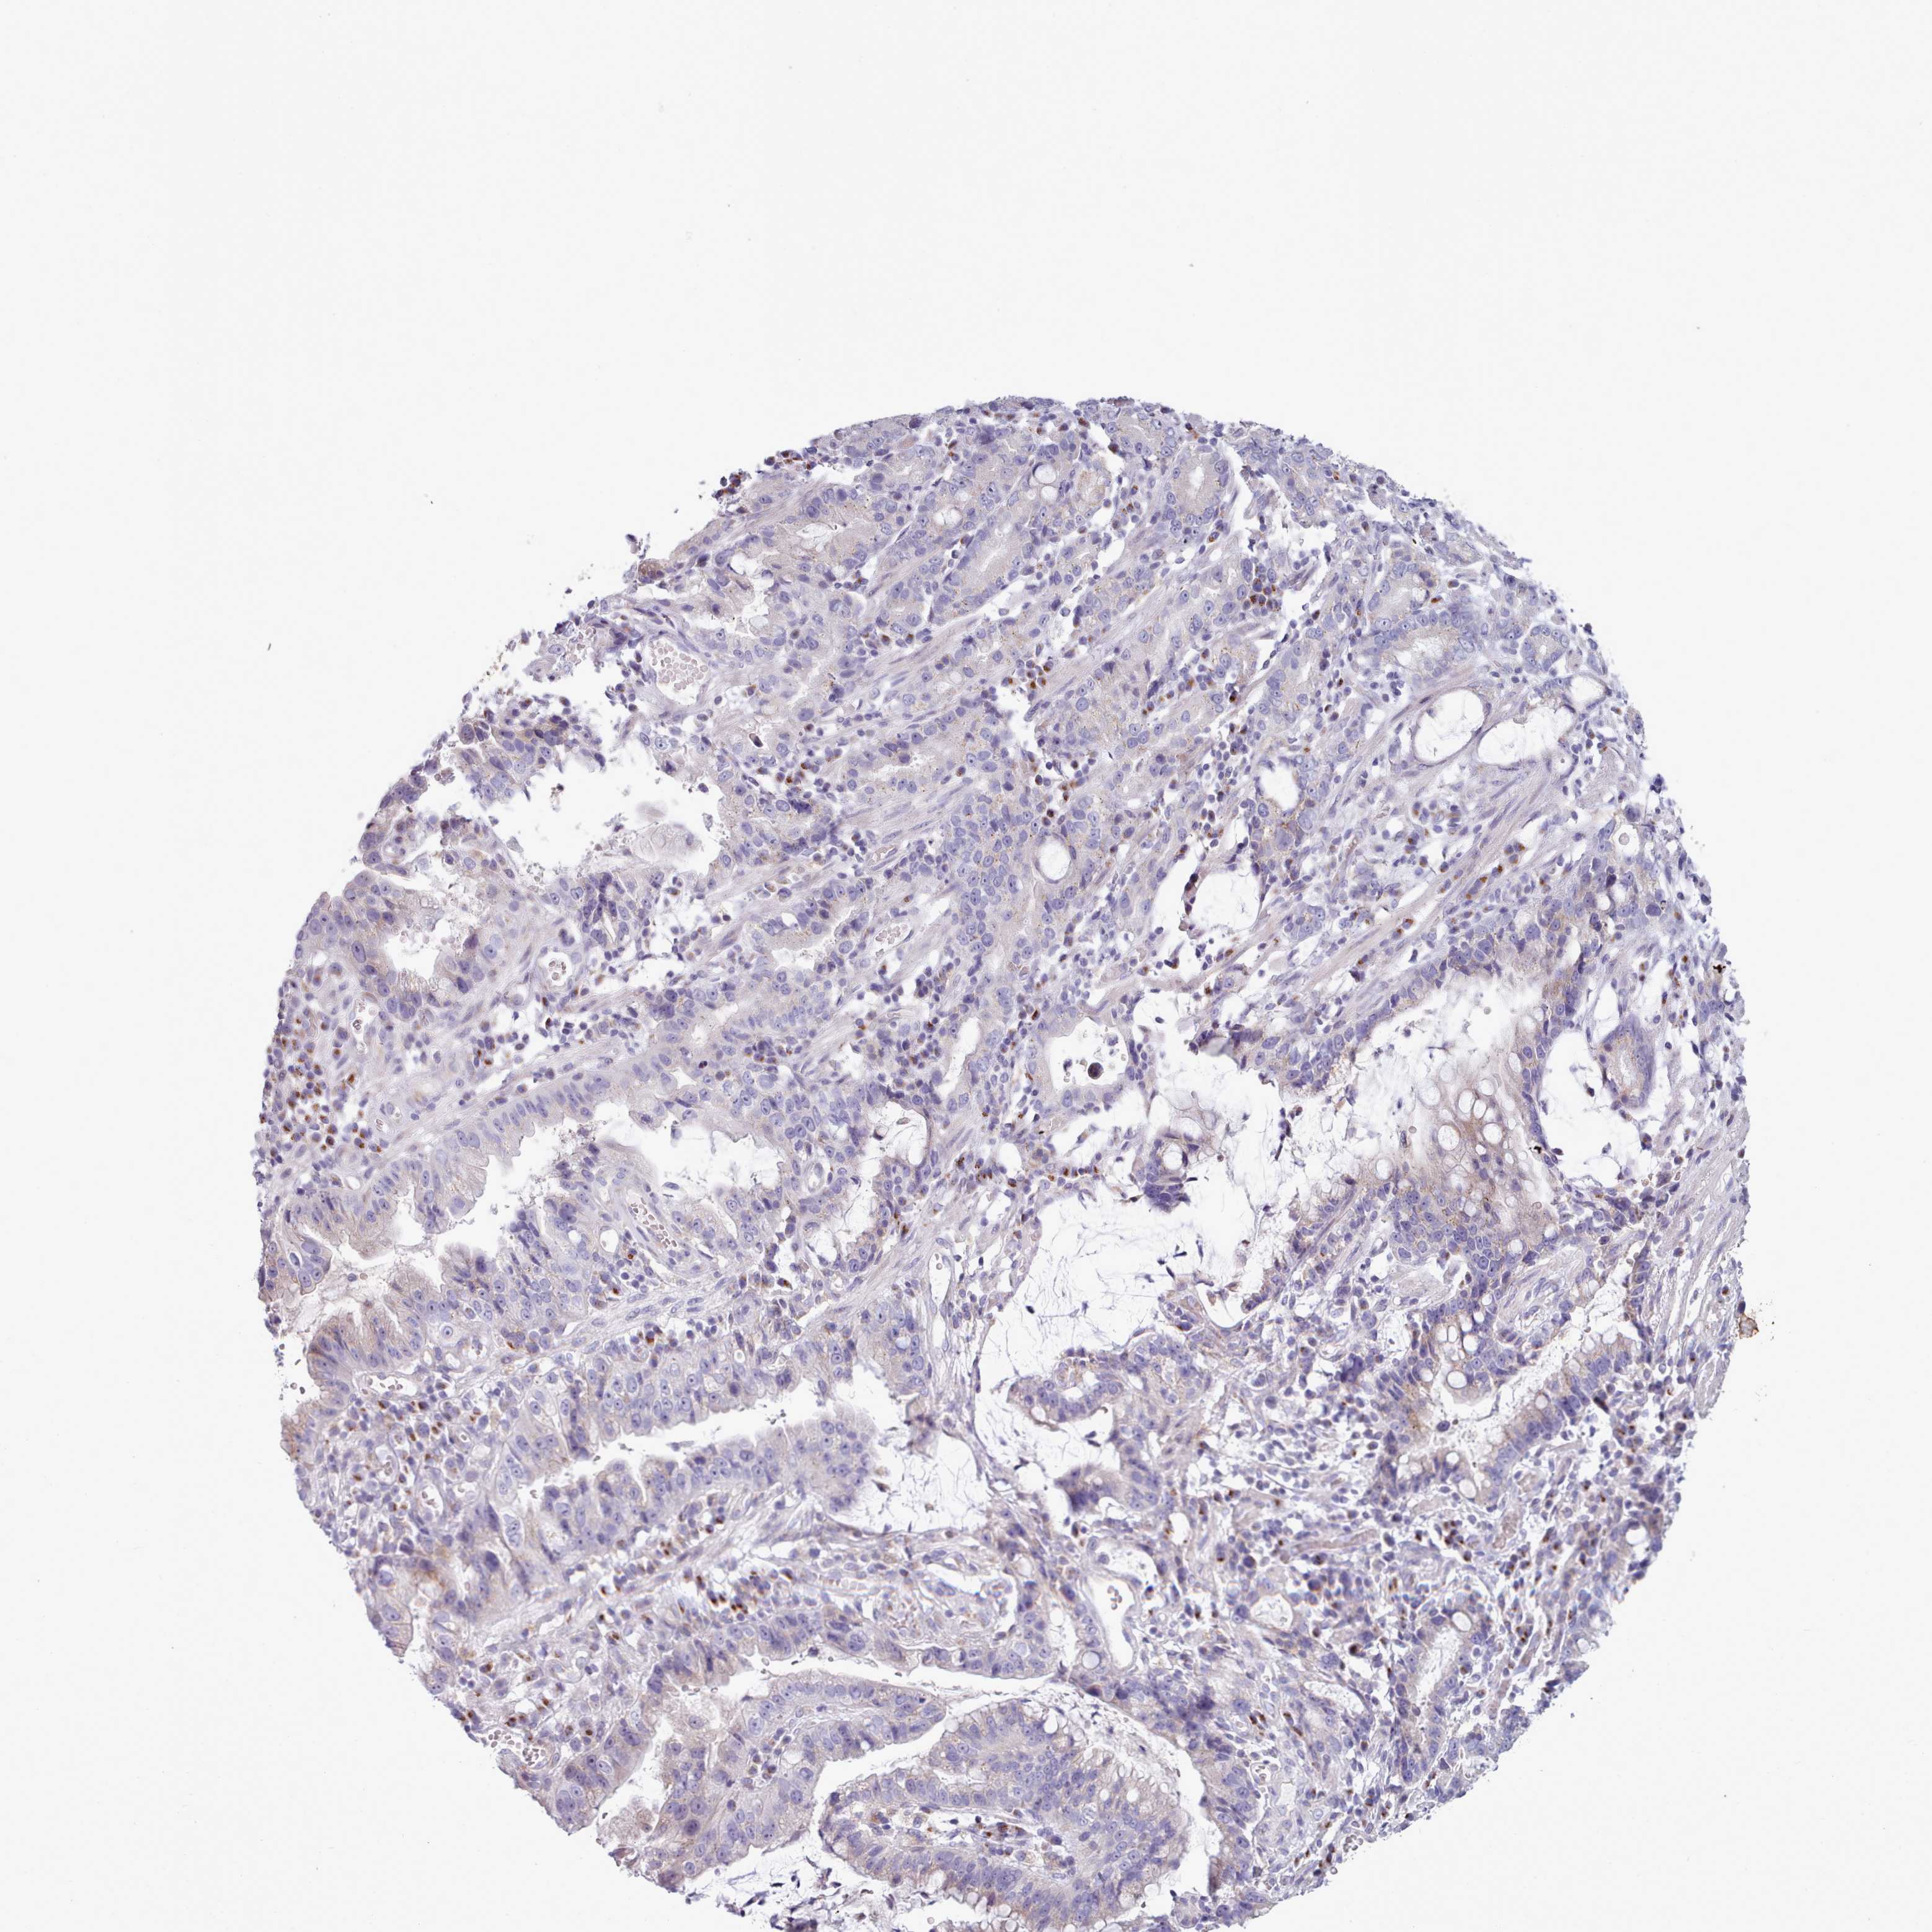

STOMACH CANCER - Protein expressioni

A mouse-over function shows sample information and annotation data. Click on an image to view it in a full screen mode. Samples can be filtered based on level of antibody staining by selecting one or several of the following categories: high, medium, low and not detected. The assay and annotation is described here.

Note that samples used for immunohistochemistry by the Human Protein Atlas do not correspond to samples in the TCGA dataset.

Antibody stainingi

Antibody staining in the annotated cell types in the current human tissue is reported as not detected, low, medium, or high, based on conventional immunohistochemistry profiling in selected tissues. This score is based on the combination of the staining intensity and fraction of stained cells.

Each image is clickable and will lead to virtual microscopy that enables deeper exploration of all samples and also displays staining intensity scores, fraction scores and subcellular localization as well as patient and tissue information for each sample.

Antibody HPA049340

Staining

High

Medium

Low

Not detected

Intensity

Strong

Moderate

Weak

Negative

Quantity

>75%

75%-25%

<25%

None

Location

Nuclear

Cytoplasmic/membranous

Cytoplasmic/membranous,nuclear

Adenocarcinoma, NOS